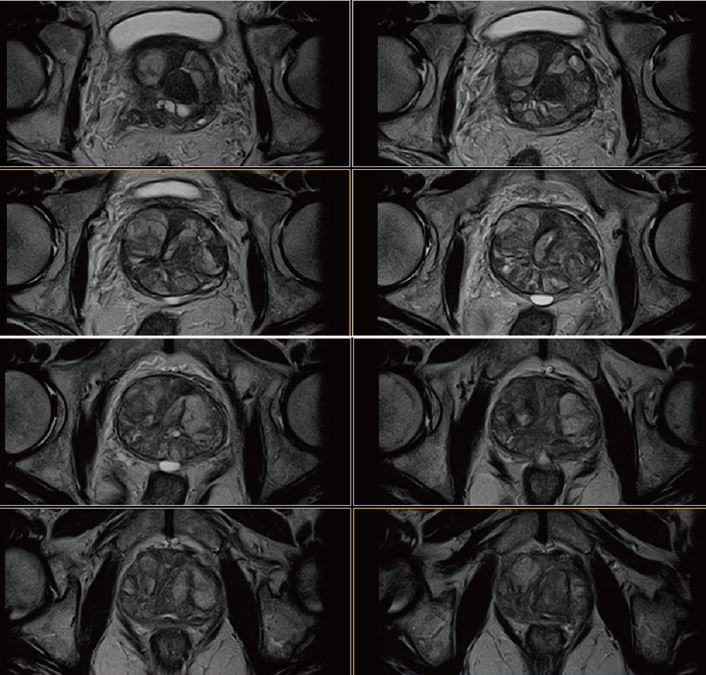

Випадок 3: PI-RADS 4

• Розміри передміхурової залози 5,3 × 3,5 × 3,4 см, об’єм приблизно 33 см3. Стандартний ZT-протокол виявив кістозностромальну пухлину, без макровузлів, з добре вираженою капсулою.

• Периферична зона має нормальну товщину, з гетерогенним сигналом, гіпосигнал помітний на Т2 та на карті ADC (Рис. 10 та 11) локалізується ззаду зліва від середини простати. Не виявлено зони гіпер-концентрації на динамічному скануванні або гіперсигналу при дифузії. (Рис. 11 та 12).

•   Капсула заповнена. Передміхурові кути прямої кишки вільні.

• Відсутні ознаки лімфаденомегалії.

Рис. 11. Аксіальне DWI – A=b0, B=Iso b800, C=Iso b1000 e, D=Iso ADC (за протоколом mpMR).

Рис. 12. Динаміка. Аксіал (12 фаз) : A=1a phase pre, B=3a phase pos, C=6a phase pos, D=12a phase (згідно протоколу m pMR)

Випадок 4: PI-RADS 3

• Розмір передміхурової залози 5,1 × 3,6 × 3,8 см, об’єм приблизно 36 см3. Стандартний ZT-протокол виявив кістозностромальну пухлину, без утворення макровузлів, з чітко вираженою  капсулою.

• Є дискретне підвищення  дна сечового міхура.

• Відзначається дискретне заднє відхилення передміхурової частини уретри.

• Периферійна зона має нормальну товщину, з гетерогенним сигналом, відзначаться область гіпосигналу на зображеннях Т2 та карті ADC. (Рис. 14 та 15) розміром 1.0, яка локалізована в лівій апікальній зоні. Не виявлено зони гіпер-концентрації на динамічному скануванні або гіперсигналу при дифузії. (Рис. 15 та 16).